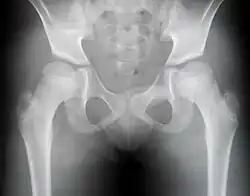

Cette maladie se manifeste d'abord par des douleurs articulaires des hanches apparaissant souvent dans l'enfance. La marche est progressivement perturbée et aboutit à une infirmité. L'état général est bon et il n'existe aucune manifestation extra articulaire. Le signe radiologique majeur est l'aplatissement de l'épiphyse de la tête fémorale.